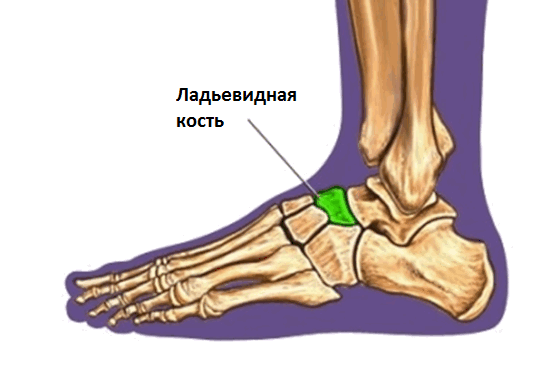

Перелом ладьевидной кости

Переломы ладьевидной кости стопы – редкая патология в общей популяции, но широко представлена в среде легкоатлетов и людей, занимающихся спортом, связанным с бегом и прыжками.

Переломы ладьевидной кости стопы подразделяются на две основные группы: травматические переломы и стресс-переломы. Травматические переломы в свою очередь подразделяются на отрывные переломы, переломы бугристости и переломы тела ладьевидной кости.

Ладьевидная кость анатомически предрасположена к стресс-переломам. Она имеет вогнутую форму и зажата между головкой таранной кости с одной стороны и тремя клиновидными костями с другой. Во время толчка стопой ладьевидная кость испытывает высокие сжимающие нагрузки. Помимо такого физиологического импинджмента, ладьевидная кость характеризуется довольно бедным кровоснабжением, с водораздельной зоной как раз в средней своей части.